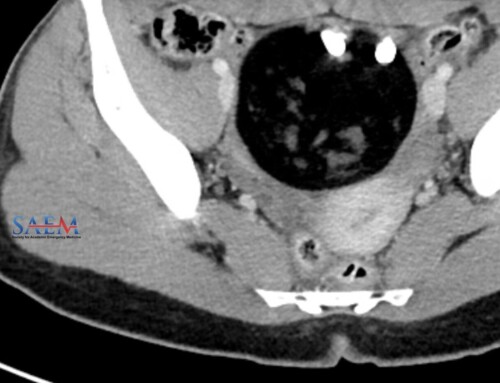

Although history, physical, and lab tests are obtained for patients with first trimester vaginal bleeding and abdominal pain, none compare to the utility of bedside ultrasonography. Today’s PV card reviews the transabdominal approach to the focused pregnancy ultrasound and was written by Drs. Matt Lipton, Mike Mallon, and Mike Stone.

PV Card: Focused 1st Trimester Pregnancy Transabdominal Ultrasound